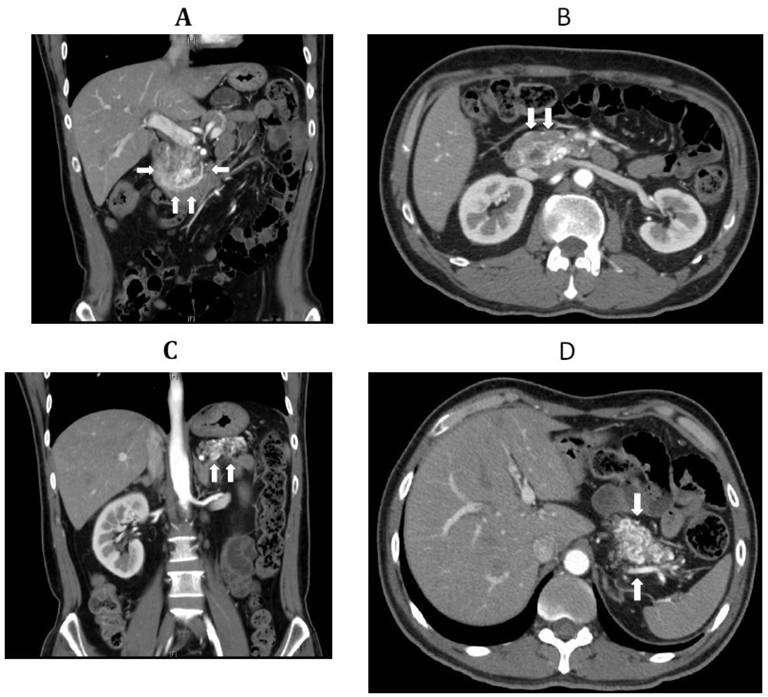

Patient refused upper gastrointestinal endoscopy. Contrast-enhanced computed tomography (CT) scan showed two hypervascular masses involving the pancreatic head and tail (Figure 1: A-D). The CT findings were suspicious for arteriovenous malformations, and accordingly, patient was scheduled for diagnostic celiac and mesenteric angiogram studies.

Figure 1. Contrast-enhanced computed tomography (CT) scans of the abdomen showing: two proliferating hypervascular masses involving the pancreatic head (A. coronal section; B. transverse section; (white arrows)) and tail (C. coronal section; D. transverse section; (white arrows)). |